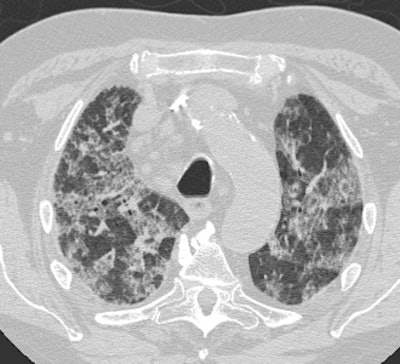

Diffuse Alveolar Damage: The patient below was admitted to the intensive care unit with increasing dyspnea. HRCT imaging revealed patchy areas of ground glass opacity and consolidation within the lungs bilaterally. There were prominent underlying reticulations within the areas of airspace disease. An open lung biopsy was performed and demonstrated diffuse alveolar damage. The etiology was not clinically apparent. |

![]() ![]() |